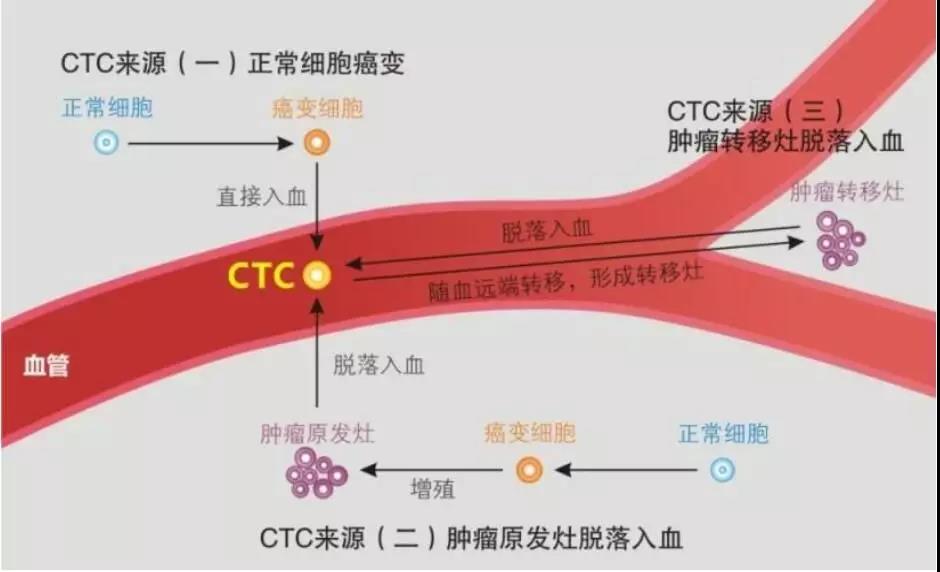

这表明肿瘤病人体内,一定发生了或正在进行一种神秘的肿瘤转移过程,一些具有增殖和转移潜力的癌细胞,从肿瘤上脱离,侵入血管并存活于血流之中。

现代医学已经明确,循环肿瘤细胞(CTC)被定义为存在于循环血流中来源于原发肿瘤或转移肿瘤的癌细胞。在循环流动的血液中筛查癌细胞CTC是确定结直肠癌早期诊断、评估有效治疗和预測疾病发展后果的一项指标。

要回答这两个问题,我们先来了解一下结直肠肿瘤细胞在血管中流动情况。一些结直肠肿瘤细胞从原发病灶脱落,侵入血管,进入血流,这些细胞主要通过门静脉系统流入到肝脏,然后到达下腔静脉,同时也会有一些癌细胞通过阴部静脉或淋巴管路进入腔静脉,在此过程中,就有癌细胞留驻在肝脏,形成肝转移癌。

癌细胞从下腔静脉进入右心,并被输注到肺内,经过肺血管网络,一部分癌细胞留驻在肺内,形成结直肠癌肺转移癌。

从肺静脉回流到左心的血液,被射进主动脉,然后血液就快速地分布到全身,血液中的癌细胞,就被送往全身,并可能在体内某个部位或多个部位形成转移肿瘤,比如骨转移,脑转移,肾转移等。

经过四肢和躯干的血液,回流入静脉,并逐渐进入上、下腔静脉进入右心。

进入血流的癌细胞,有很多因为癌细胞内部控制程序的作用而死去,这种过程,是我们经常听到的一个名词,叫“细胞凋亡”。只有哪些具有转移和增殖能力的癌细胞,会驻留在肝脏、肺、骨骼等器官形成肿瘤转移。